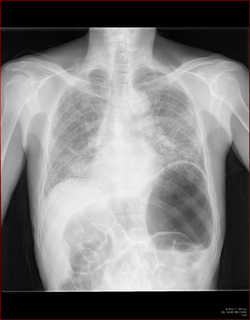

例えば肺の大きさ。

volume

lossや反対に過膨張などの所見は、圧倒的に胸部正面写真がわかりやすいですね。